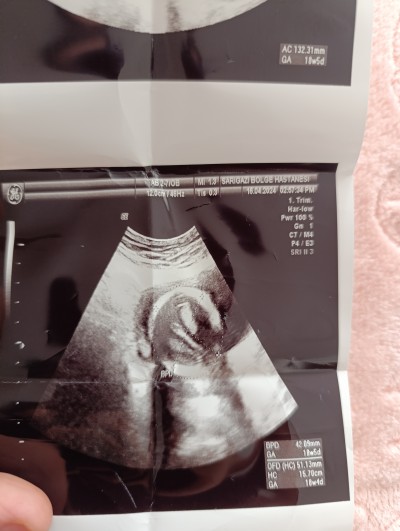

Bilgisini olan yazarmi

Hiiiic anlamam kuzum ama erkek geçti içimden.

Sağlıkla al kucağına insallah ♥️